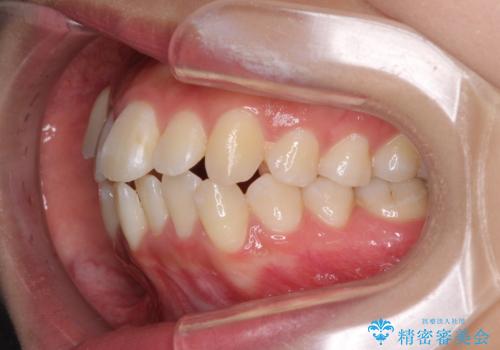

前歯の正中のズレを改善 目立たないワイヤー装置での抜歯矯正

- 八重歯を気にして来院された患者様です。

上下ともに前突感と叢生が認められ、上顎の正中が著しく右側にずれていたため、上下左右第一小臼歯4本を抜歯し、ワイヤー矯正にて治療を行うこととしました。

移動量が多かったため、治療期間は通常より半年~1年ほど長くかかりましたが、上下の正中をほぼ同じ位置にまで移動させることができました。